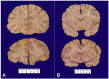

Snyder-Robinson syndrome, also known as spermine synthase deficiency, is an X-linked intellectual disability syndrome (OMIM #390583). First described by Drs. Snyder and Robinson in 1969, this syndrome is characterized by an asthenic body habitus, facial dysmorphism, broad-based gait, and osteoporosis with frequent fractures. We report here a pediatric autopsy of a 4 year old male with a history of intellectual disability, gait abnormalities, multiple fractures, and seizures previously diagnosed with Snyder-Robinson syndrome with an SMS gene mutation (c.831G>T:p.L277F). The cause of death was hypoxic-ischemic encephalopathy secondary to prolonged seizure activity. Although Snyder-Robinson syndrome is rare, the need to recognize clinical findings in order to trigger genetic testing has likely resulted in under diagnosis.